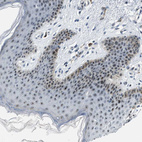

Immunohistochemical staining of human skin shows strong nuclear positivity in squamous epithelial cells.